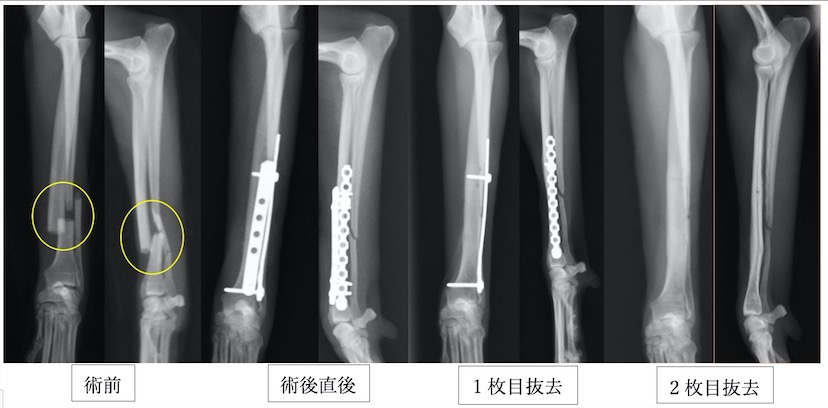

イタリアングレーハウンドの橈尺骨骨折です。2.0mmスクリューを使用しています。

上の3症例ともにやや中央寄りの先端部の橈尺骨の横骨折(遠位骨幹部橈尺骨横骨折)です。直線のプレートを使用しています。